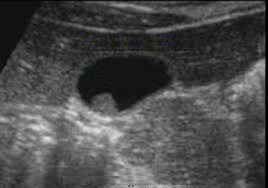

Image de

adenomateuse polyppoide isoechogenes de type sessile

: Image echographique en coupe longitudinale de la

vesicule biliaire |